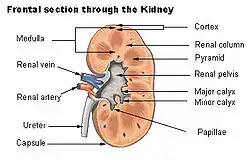

Renal papilla Frontal section through the kidney

The renal medulla (Latin: medulla renis 'marrow of the kidney') is the innermost part of the kidney. The renal medulla is split up into a number of sections, known as the renal pyramids. Blood enters into the kidney via the renal artery, which then splits up to form the segmental arteries which then branch to form interlobar arteries. The interlobar arteries each in turn branch into arcuate arteries, which in turn branch to form interlobular arteries, and these finally reach the glomeruli. At the glomerulus the blood reaches a highly disfavourable pressure gradient and a large exchange surface area, which forces the serum portion of the blood out of the vessel and into the renal tubules. Flow continues through the renal tubules, including the proximal tubule, the loop of Henle, through the distal tubule and finally leaves the kidney by means of the collecting duct, leading to the renal pelvis, the dilated portion of the ureter.

Renal pyramids (or malpighian pyramids or Malpighi's pyramids named after Marcello Malpighi, a seventeenth-century anatomist) are cone-shaped tissues of the kidney. In humans, the renal medulla is made up of 10 to 18 of these conical subdivisions.[4] The broad base of each pyramid faces the renal cortex, and its apex, or papilla, points internally towards the pelvis. The pyramids appear striped because they are formed by straight parallel segments of nephrons' Loops of Henle and collecting ducts. The base of each pyramid originates at the corticomedullary border and the apex terminates in a papilla, which lies within a minor calyx, made of parallel bundles of urine collecting tubules.

The renal papilla is the location where the renal pyramids in the medulla empty urine into the minor calyx in the kidney. Histologically it is marked by medullary collecting ducts converging to form a papillary duct to channel the fluid. Transitional epithelium begins to be seen.